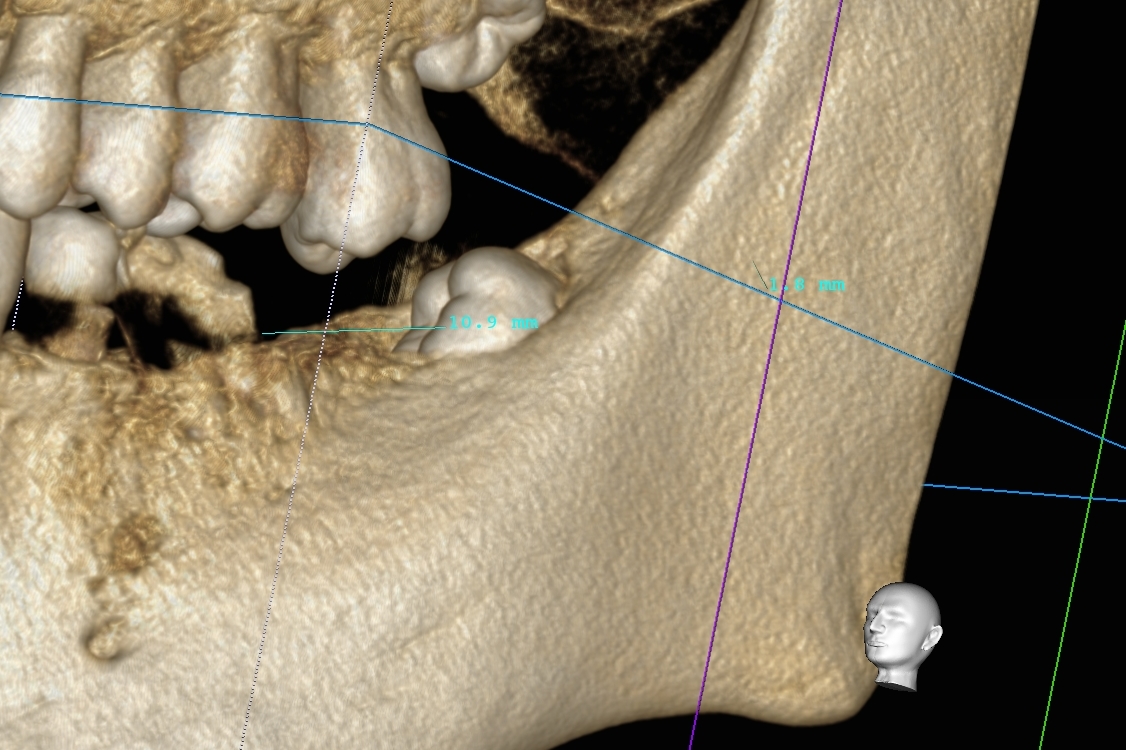

今回の患者様は、以前から入れ歯の治療でお悩みを抱えていらっしゃいました。何件もの歯科医院で入れ歯治療を繰り返し、時には紹介された大学病院でも入れ歯を作製。なかなか満足できる入れ歯に出会うことができない。そんな中、以前の勤務先で私が担当医として入れ歯治療を行い、今までの悩みが解決できたとのことで、今回来院に至ったそうです。このお話は、本日患者様が教えてくださいました(^^♪

入れ歯の治療は困難なことは多いです。

私は何が原因で患者様がお悩みを抱えていらっしゃるのか、可能な限りお話を伺った上で、正確な診査・診断の下、治療方針をお伝えするようにしています。